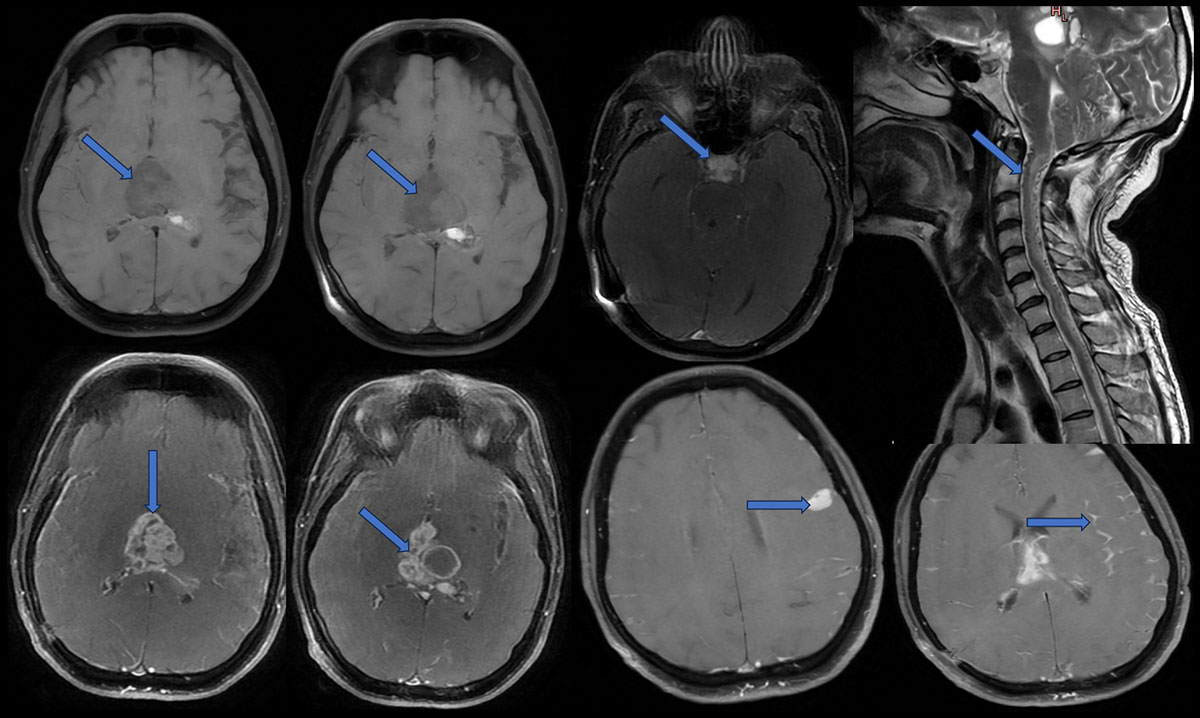

MRI:

- Heterogeneous, multiloculated solid-cystic lesion with calcifications and haemorrhage in pineal region causing mass effect of brainstem, the solid component shows intense enhancement and the cystic areas show peripheral enhancement.

- Similar solid lesion seen in sellar-suprasellar region, shows intense contrast enhancement.

- Multifocal areas of nodular and smooth leptomeningeal enhancement predominantly along the cerebral hemispheres (L>R).

- There is leptomeningeal enhancement along the visualised cervical cord – leptomeningeal drop metastasis.

Incidental finding: multiple flow voids seen along the cervical and thoracic cord, no nidus and oedematous cord signal changes secondary to venous congestion – dural AV fistula.